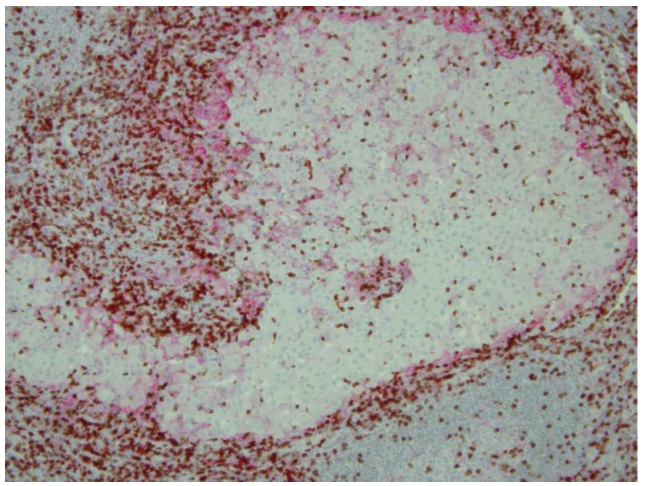

Fig. 19.1 CD8+T细胞旁边的黑色素瘤细胞表达PD-L1。通过免疫组化染色标记黑色素瘤淋巴结病变中的CD8+T细胞(棕色)和黑色素瘤细胞(PD-L1, 红色)。

在表面TCR与携带黑色素瘤抗原肽的MHC-I复合物结合后,黑色素瘤特异性CD8+T细胞被激活,随后释放干扰素γ,诱导周围黑色素瘤细胞表达PD-L1(也称为B7-H1和CD274),如Fig. 19.1所示。PD-L1与CD8+T细胞上的抑制性共受体PD-1结合,从而削弱T细胞的效应器功能(细胞溶解颗粒和细胞因子释放),抑制其增殖。此外,PD-1还能与PD-L2结合,但是在黑色素瘤细胞上检测不到这种结合。正常情况下,T细胞中的PD-1信号对机体维持自身免疫耐受具有重要意义,PD-1基因敲除小鼠出现自发的自身免疫反应证明了这一点。因此,PD-1是抑制CD8+T细胞功能的重要检查点,黑色素瘤细胞通过表达PD-L1,获得了直接降低T细胞活性的能力(Fig. 19.2)。而在从肿瘤组织和黑色素瘤患者外周血中分离出的新抗原特异性CD8+T细胞上,也发现了PD-1的表达,这为开发阻断PD-1和PD-L1之间相互作用的治疗策略提供了理论基础(Fig. 19.2)。